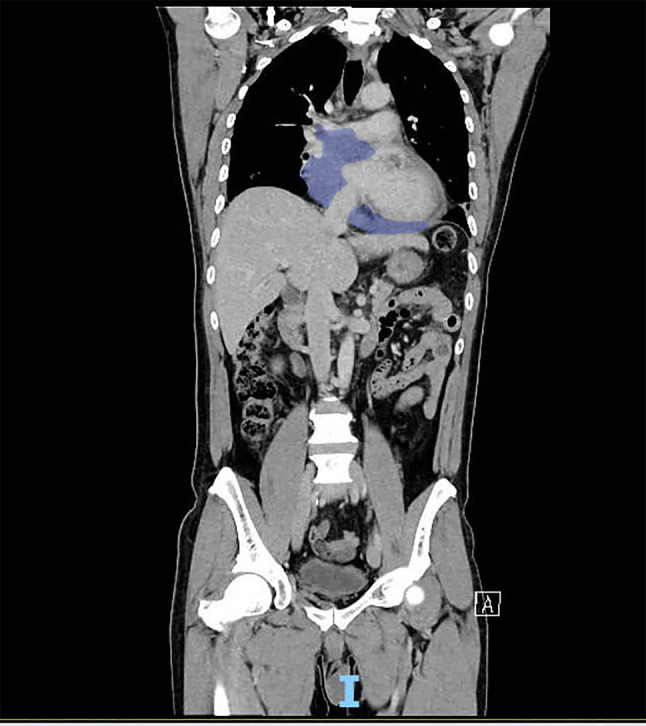

Case report: This case describes a 59-year-old patient who presented with a cardiac mass and exhibited signs of superior vena cava syndrome, including odynophagia, dysphagia, hoarseness, and constitutional symptoms. Subsequent investigations revealed a primary malignant spindle cell sarcoma originating from the pericardium.